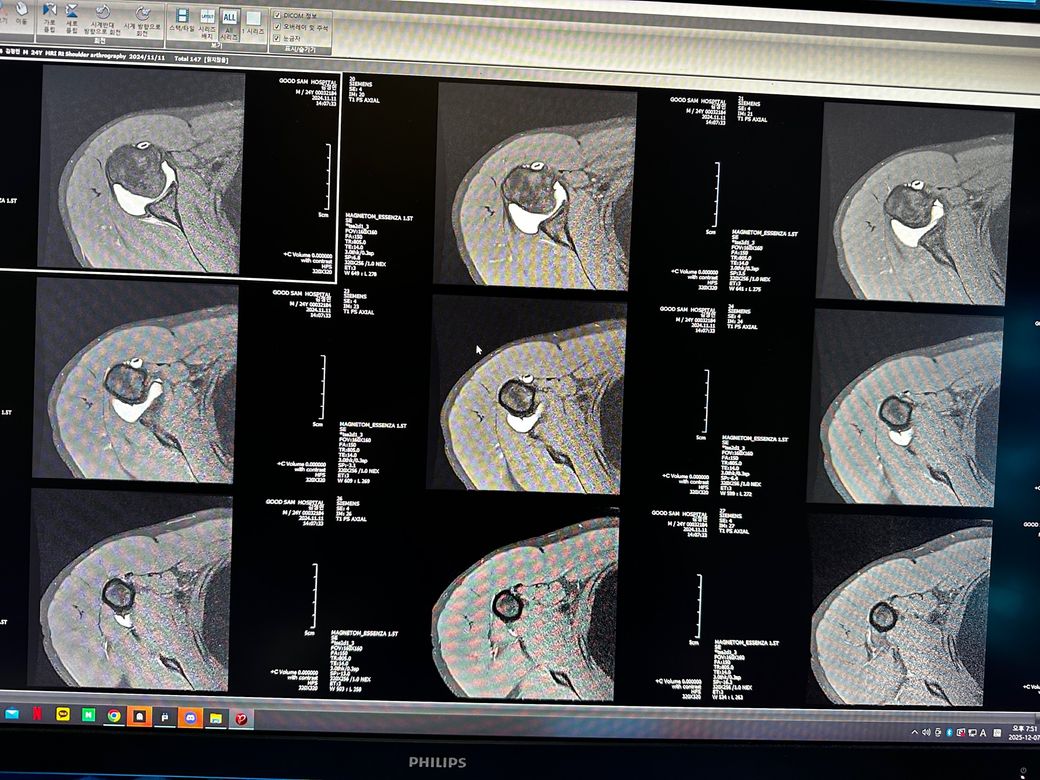

오른쪽어깨 관절mri좀 봐주세요 사진첨부입니다

오룬쪽어깨관절 엠알아이 결과좀 봐주세요

오른쪽어깨관절부분입니다

관절입니다

• 4번 째 사진

• 5번 째 사진

• 6번 째 사진

조영제가 들어간 것으로 보이며, "회전근개(특히 극상근) 파열이나 큰 손상은 뚜렷하게 보이지 않는 편"입니다.

관절와순(Labrum) 주변에 조영제가 퍼져 보이지만, "명확한 파열 소견은 사진만으로 단정 어렵고 경미한 손상.염증 가능성"은 있습니다.

관절 안쪽에 "약한 염증/활액 증가"는 있어 보이며, 충돌증후군 초기 형태 가능성이 있습니다.